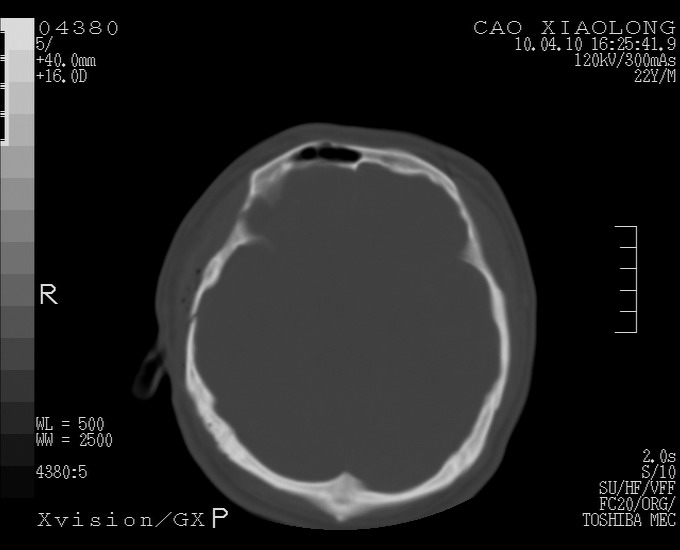

以下是引用随光逐影在2010-4-11 11:00:00的发言:[br]1)左侧额颞顶部硬膜下血肿。2)蛛网膜下腔出血。3)右侧颞顶部颅骨线形骨折。[br][br]20小时后复查:左侧额颞叶脑挫裂伤;左侧额颞顶部硬膜下血肿及蛛网膜下腔出血有吸收表现;右侧颞顶部颅骨线形骨折。[br]